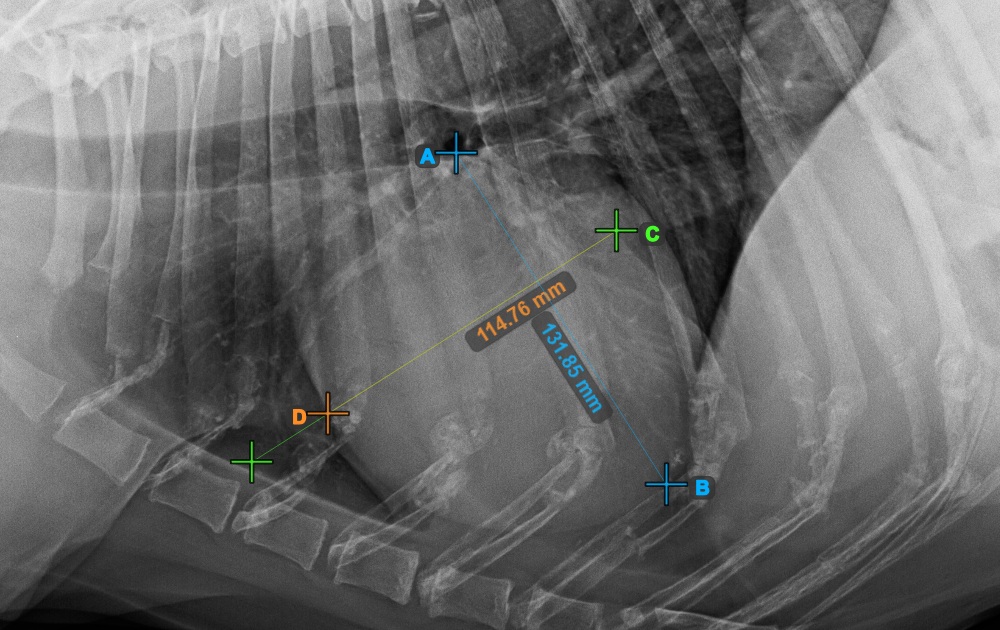

Vervollständigen Sie die Längsachse des Herzens, indem Sie den Apex-Punkt in der Nähe der Herzunterseite markieren.

Das Bild unten zeigt die typische Platzierung des Apex-Punkts.

Fahren Sie mit der Messung fort, indem Sie den breitesten rechten (vorderen) Punkt der Kurzachse des Herzens markieren.

Das Bild unten zeigt die typische Platzierung des vordersten Punkts auf der Kurzachse des Herzens.

Vervollständigen Sie die Kurzachse des Herzens, indem Sie den breitesten linken (hinteren) Punkt markieren.

Das Bild unten zeigt die typische Platzierung des hintersten Punkts auf der Kurzachse des Herzens.